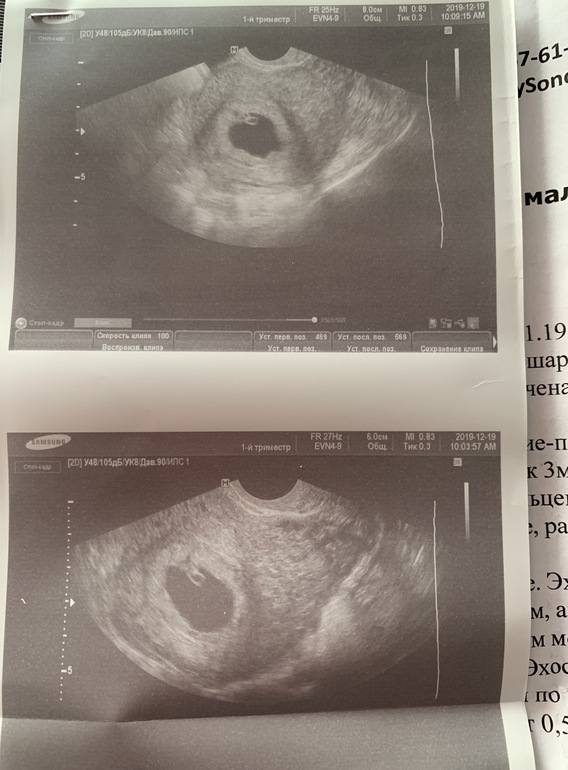

Пришла на приём, сделали узи: СВД 18 мм, ктр 6 мм, сб +, жт хорошее и все бы отлично , соответсвует сроку... но!

Девочки! Плодное яйцо в одной из проекций узи имеет такие неровные контуры,

честно сказать, я такого никогда не видела ! (Фото прилагаю) Они прям очень деформированы, при том в другой проекции - все супер, ровненькое яичко,

Г сказала, что такие контуры, тревожный знак, хоть и тонуса нет.... в общем, наблюдение и контроль через неделю (я не планировала так часто на узи ходить!, но и пропустить что-либо опасное не хочется).